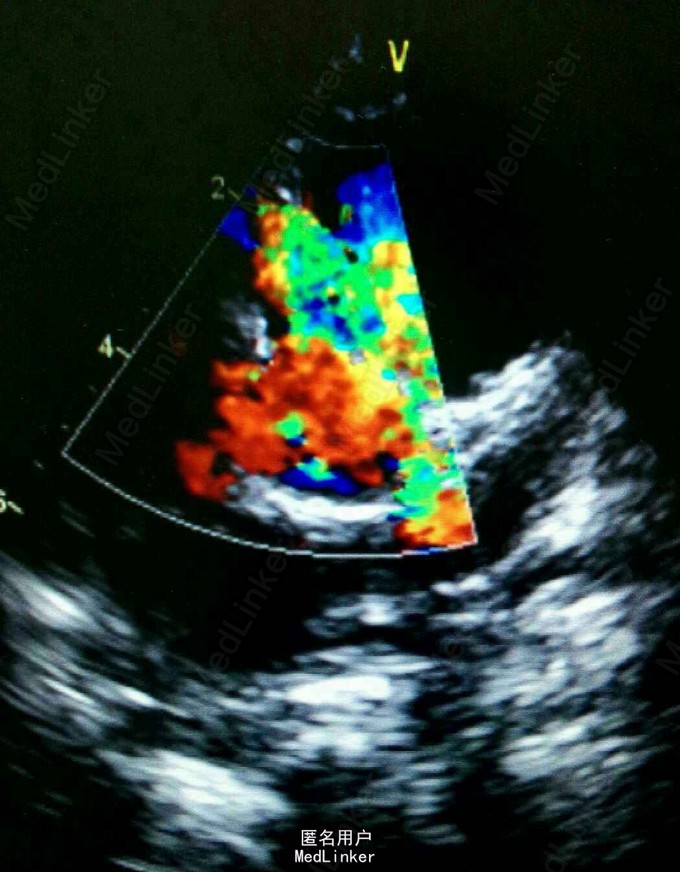

双肺呼吸音粗,可闻及中量哮鸣音及湿罗音。腹部彭隆,肝脾未触及。辅查:B超提示ASD,PDA,三尖瓣轻度反流,肺动脉高压(中度)。血象高,以淋巴为主。

诊断为:高原性心脏病,慢性肺炎,先心。 处理:予小剂量多巴胺强心,利尿。予美洛西林钠舒巴坦钠联合头孢硫脒抗感染治疗。营养心肌,雾化等对症。支气管镜提示喉软骨软化。加用伊可新对症。顺尔宁止咳平喘。患儿咳嗽逐渐好转。